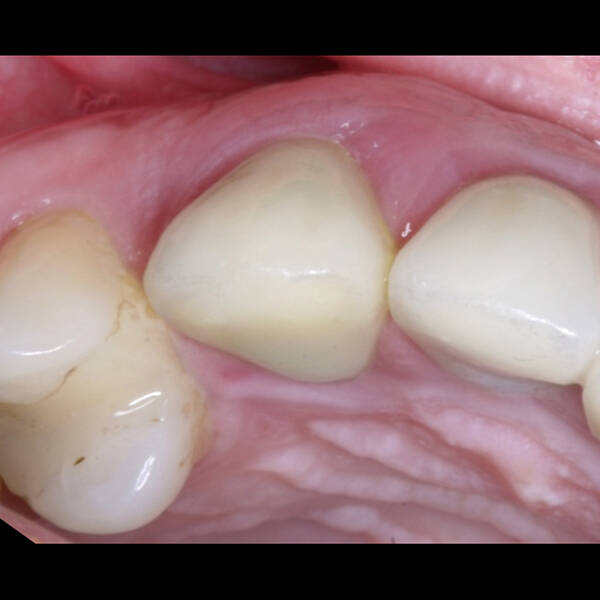

- Conforto e Estética: A prótese provisória é funcional e visualmente semelhante aos dentes naturais.